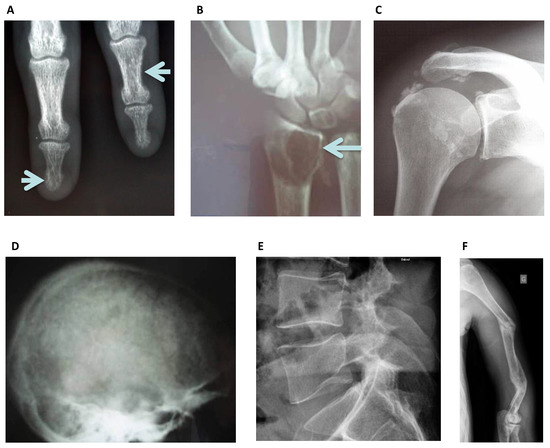

3.1. Conventional Radiography

| Plain Radiography | Bone resorption lesions Bone cysts Fractures | Sub-periosteal Subchondral Sub-tendinous Extra-skeletal calcifications All skeleton | Secondary Hyperparathyroidism Multiple Myeloma Amyloidosis Osteonecrosis Osteoporosis Calcific Uremic Arteriolopathy | All |